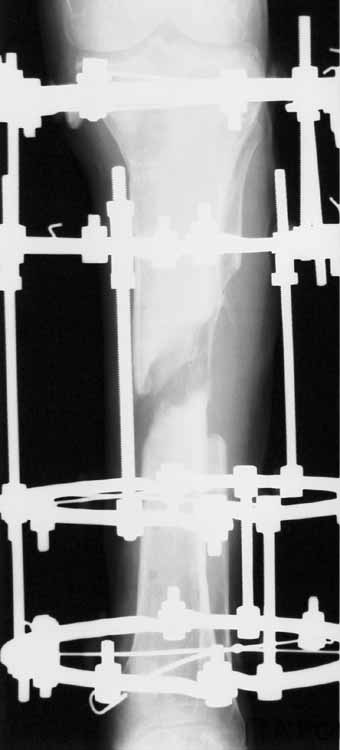

1 июня произведено удаление гвоздя, дренаж костномозгового канала, остеосинтез аппаратом Илизарова ( after 1; 2).

Ввиду относительной тугоподвижности ложного сустава и наличия признаков репаративной активности костной ткани рентгенологически, после 10 дней компрессии на стыке отломков, начали дистракцию по 1мм в день. Выписан на амбулаторное лечение. Отделяемое в нижней трети голени прекратилось, ранка закрылась. Интраоперационно и 5 дней после операции получал ципроксациллин. В июле по передней поверхности голени в зоне регенерата открылась ранка с обильным гнойным отделяемым. После локального лечения, ранка в течении двух недель эпителизировалась и полностью закрылась. Дистракцию не прекращали. (during 1, 2)

10 дней назад ранка на передней поверхности средней трети голени и по внутренней поверхности нижней трети голени, (по проекции стержня апп.Гофмана) открылись вновь. В настоящий момент отделяемого из обеих ран нет (wound1;2).

Рентгенологически определяется дистракционный регенерат удовлетворительной плотности и наличие в нем полости (now 1;2;3).

После последнего R- снимка 4 дня назад, аппарат переведен в режим фиксации.